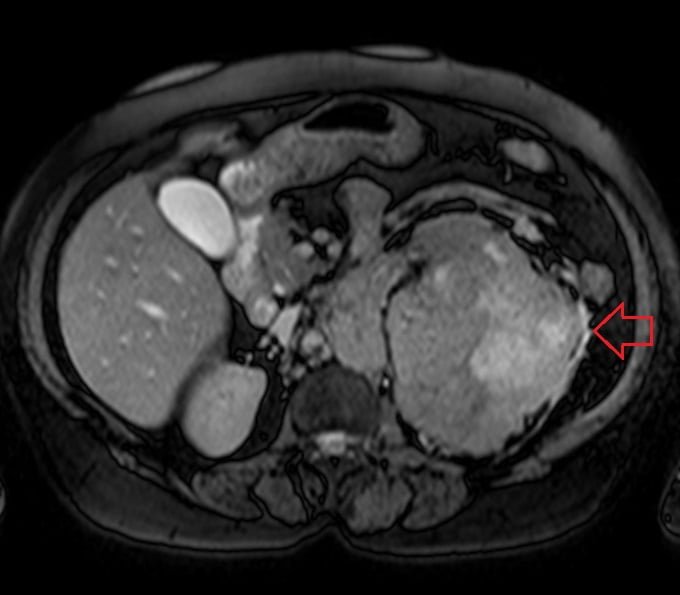

MRI abdominal pathologies FNH LIVER Haemangiomas Liver Choledocholithiasis Renal cell carcinoma Abdominal Wall AVM Gallstones Retroperitoneal desmoid Hepatocellular carcinoma (HCC)